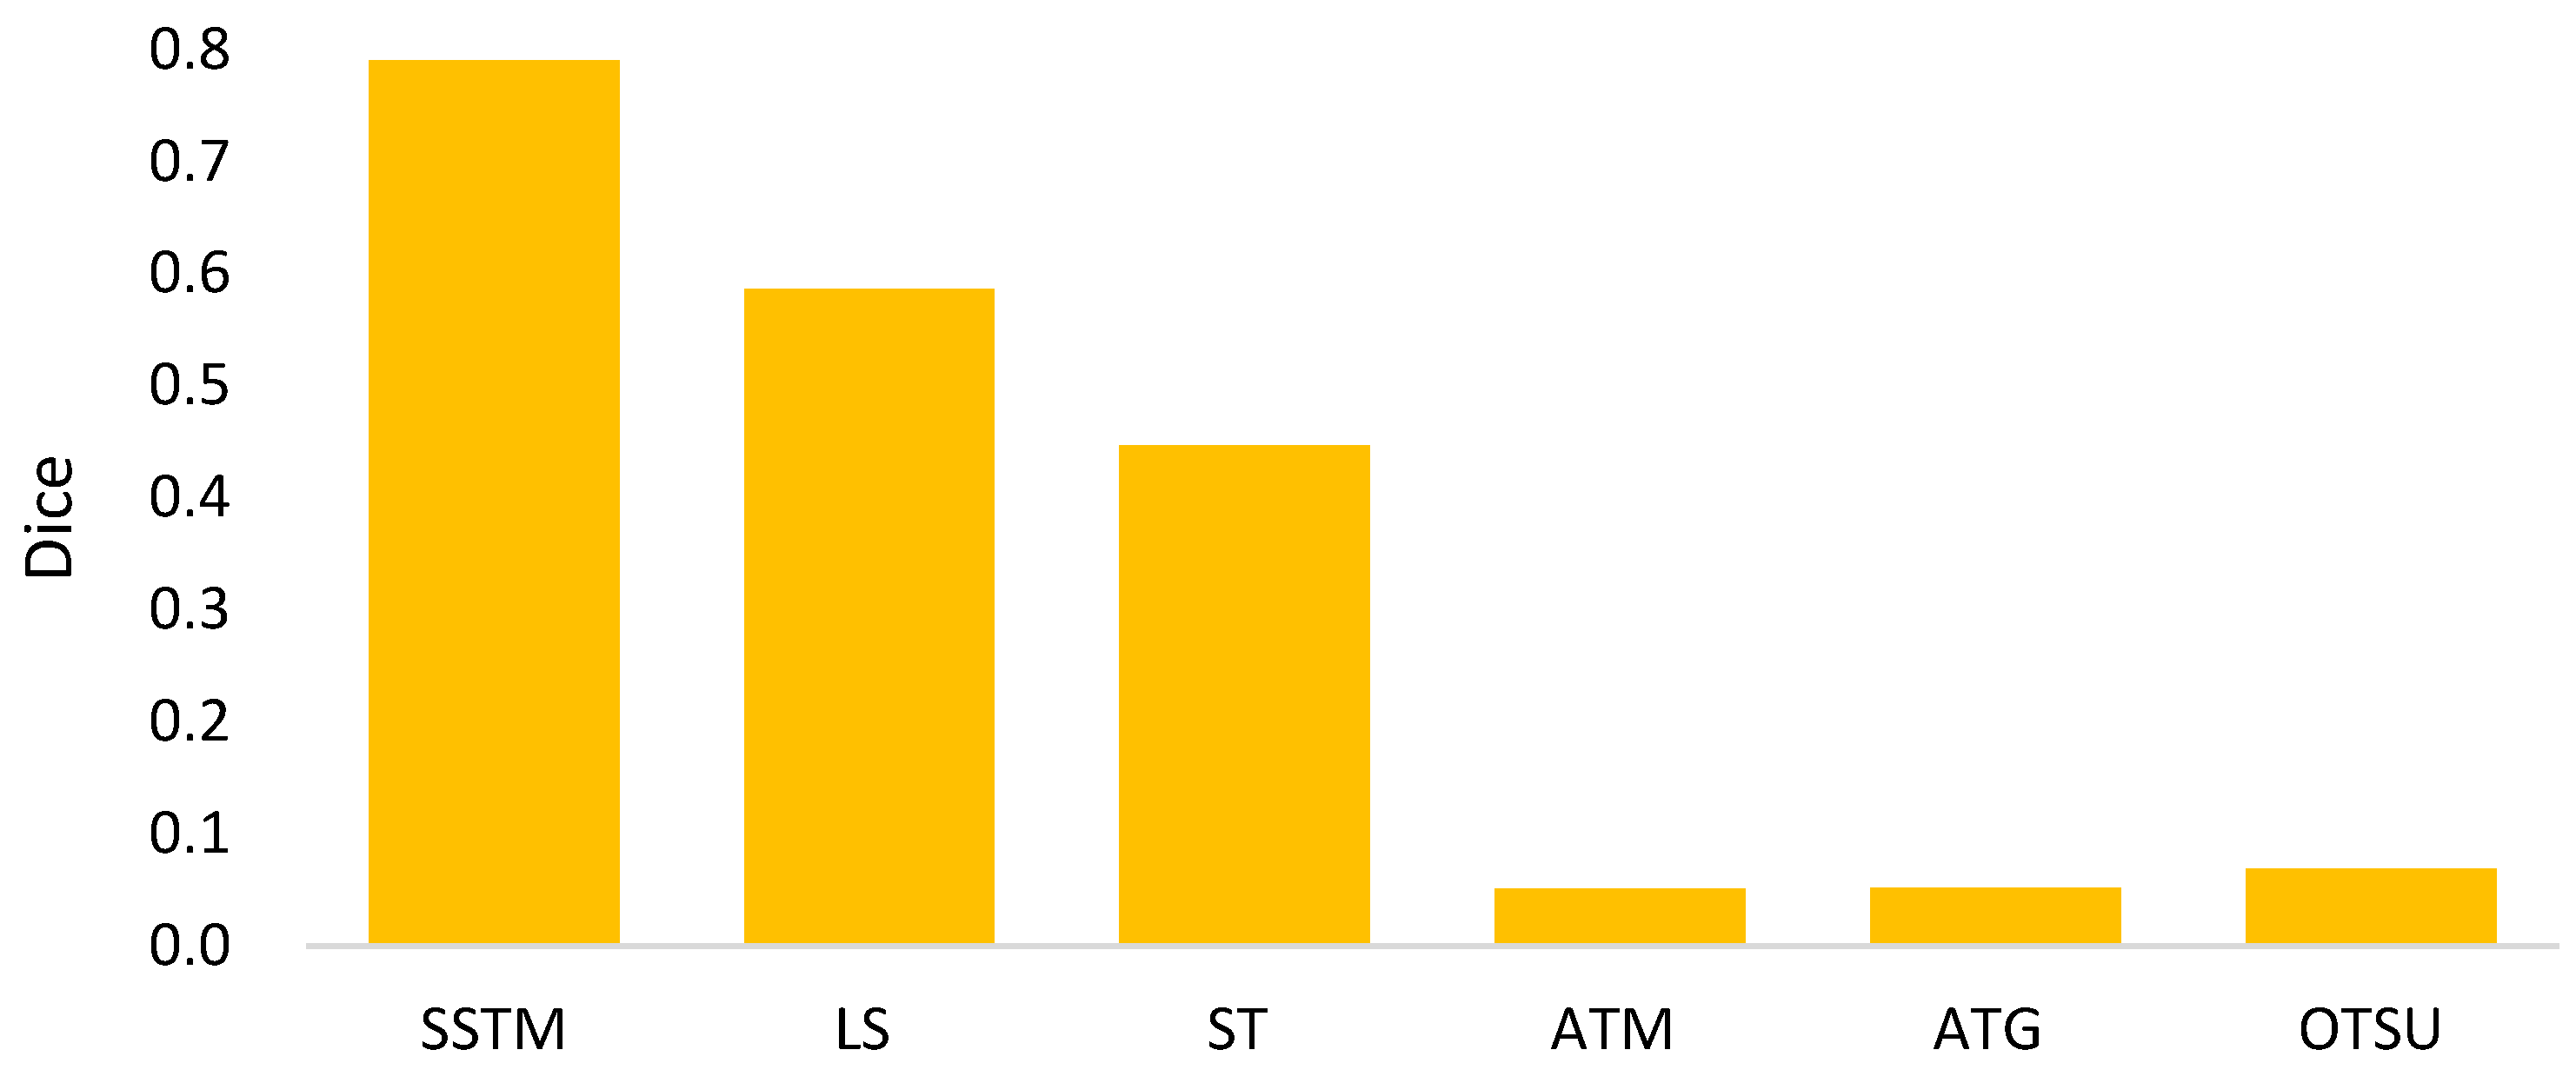

3.2.3. Comparisons with Existing Semi-Automated Segmentation Methods

- The goal of semi-automated segmentation is to provide the doctors with an efficient and effective tool for marking the nodules. Actually, most existing marking systems perform the fully automated segmentation as an initial mark. Then, it is revised by the doctor. Hence, a potential question for effectiveness differences of the proposed semi-automated segmentation and fully automated ones needs to be replied. For this question, three recent fully automated segmentation methods, including Mask-RCNN [7], Unet [24], and SeResUnet [34] were compared with the proposed method SSTM. Figure 20 reveals that the proposed SSTM achieves much better dice than the fully automated methods, reaching a dice improvement of 392.3%. The first potential reason is that the training data for the compared methods are not enough. Second, additional click information is very helpful to segmentation. In summary, this result says that the proposed idea is robust if facing small data. Moreover, it is easy and cheap. Note that all methods were executed with the same experimental settings.